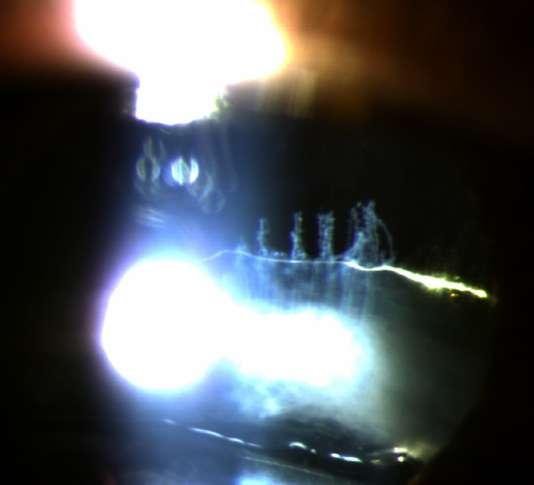

Caso aportado por Dr. Cristian Sanchez

Hombre 53 años con anteccedentes de facoemulsificación + implante de lente OD, consulta tras episodios de uveitis hipertensiva a repetición asociados a hifema del ojo derecho.

ü AV 0.7 OD

ü PIO OD: 28mmHg

ü BMC (Imagen A y B): Córna transparente, cámara anterior formada, Tyndall +, LIO in situ, transiluminación sectoriales del iris, iridotomías superior e inferior. Nevus conjuntival.

UVEÍTIS - GLAUCOMA - HIFEMA

8.C. SÍNDROME

A B

ü Gonioscopía (Imagen C): Ángulo abierto en en 270º, trabéculo con pigmento, SAP inferior

ü Fondo de ojo (Imagen D): Papila pálida con excavación 0.9. macula sana

ü El Sd. UGH es una complicación que puede aparecer en el post operatorio (precoz o tardío) luego de la implantación de un lente intraocular.

ü Se define clásicamente por la triada que su nombre comprende, aunque pueden aparecer formas incompletas.

ü La incidenccia se ha visto aumentada debido al incremento de la cirugía de cristalino, ya sea por catarata o con finalidad refractiva.

ü La patogenia se debe a la presión ejercida por los hápticos del lente intraocular (LIO) sobre el tejido uveal y puede presentarse en paciente con lentes en cámara anterior, sulcus o saco.

ü Sospechar en paciente pseudofáquico con episodios recurrentes de uveitis no filiada C D